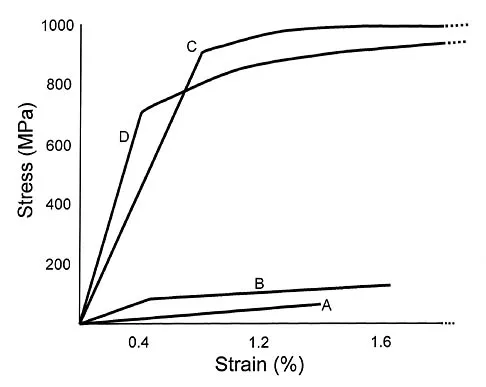

Design and manufacturing of a metal-on-metal articulation has an important influence on the tribology. Which of the following statements best characterizes the type of contact that is best for metal-on-metal articulations?

Detailed Explanation